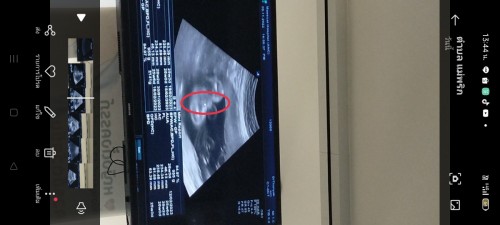

หญิงไหมคะแบบนี้...32wท้องเเรก อยากได้หญิง😁😁😘😘 ขอดูผลซาวด์ของแม่ๆหน่อยจ้า #ขอบคุณล่วงหน้านะคะ